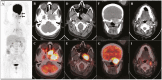

Figure 2.

A to I, Maximum intensity projection of the whole-body 18F-fluorodeoxyglucose (FDG) positron emission tomography/computed tomography (PET/CT) shows A, abnormal focus of FDG uptake in the region of the base of the skull and in the left cervical region (black arrows). B and C, Transaxial contrast-enhanced CT and fused PET/CT images localized the uptake to a heterogeneously enhancing soft-tissue mass in the left sphenoid region and extending to the pituitary fossa, apex of left temporal bone, the nasal cavity, and apex of left orbit anteriorly with a maximum standardized uptake value (SUVmax) of 35.5. D and E, The mass was seen to cause bony erosion of the left greater wing of sphenoid and the left medial and lateral pterygoid plates. F and G, In the coronal CT and fused PET/CT images, the mass has intracranial extension to the left temporal lobe. H and I, There are significant FDG-avid enlarged lymph nodes at cervical level II (white arrow, with SUVmax 11.2) and level IV on the left side.